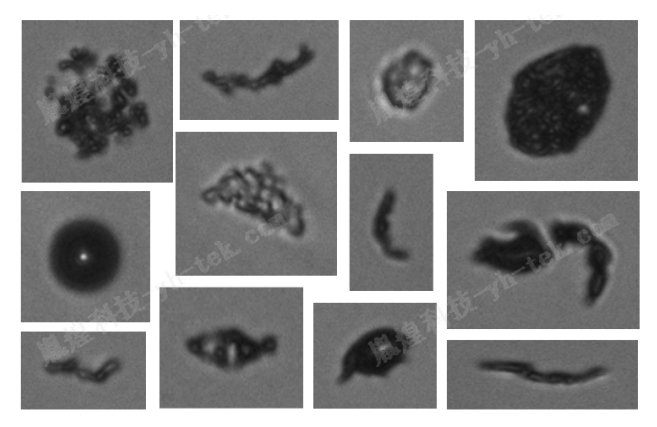

乳剂注射剂不溶性微粒检测首选方案-显微计数法!【案例分享】

乳剂注射剂是医疗领域常用的药物剂型之一,然而在使用过程中,其不溶性微粒的问题备受关注。不溶性微粒不仅可能影响药物的稳定性和有效性,还可能对患者的安全构成威胁。因此,对乳剂注射剂中不溶性微粒的检测显得尤为重要。在众多检测方法中,显微计数法因其直观、准确的特点,成为首选方案。 案例说明: 乳剂通